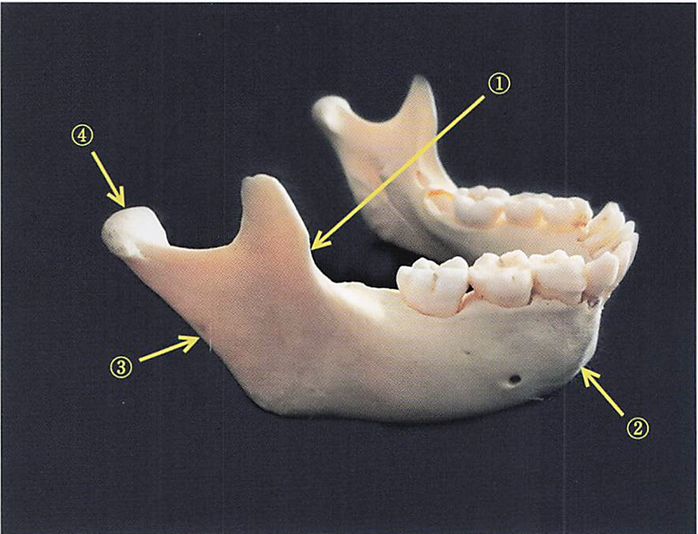

下顎骨の写真を別に示す。 成長過程で吸収するのはどれか。1つ選べ。